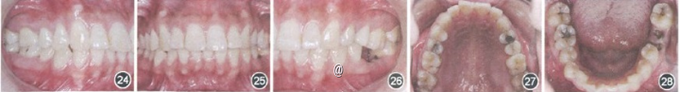

男,25岁。主诉:要求矫治牙齿前突。

检查:磨牙、尖牙均为远中关系;II度深覆骀,Ⅱ度深覆盖;36残根(图24~29)。x线片显示,38缺失。